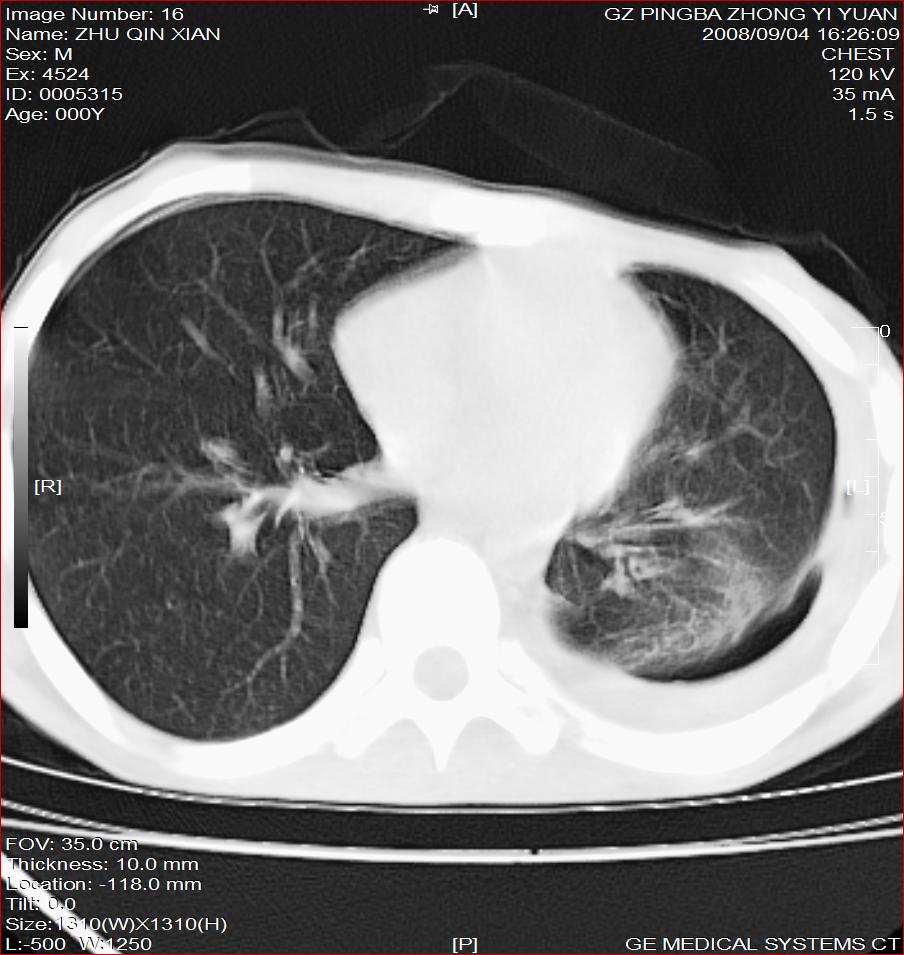

以下是引用随光逐影在2008-9-4 20:05:00的发言:[br]1)考虑两肺结核。2)左侧胸膜炎(胸膜肥厚、粘连,胸腔积液)。3)左侧局限性气胸。

以下是引用子十在2008-9-4 19:34:00的发言:[br]左上肺结核并空洞及双肺播散。节段性肺不张、胸腔积液、胸膜肥厚粘连。[br]